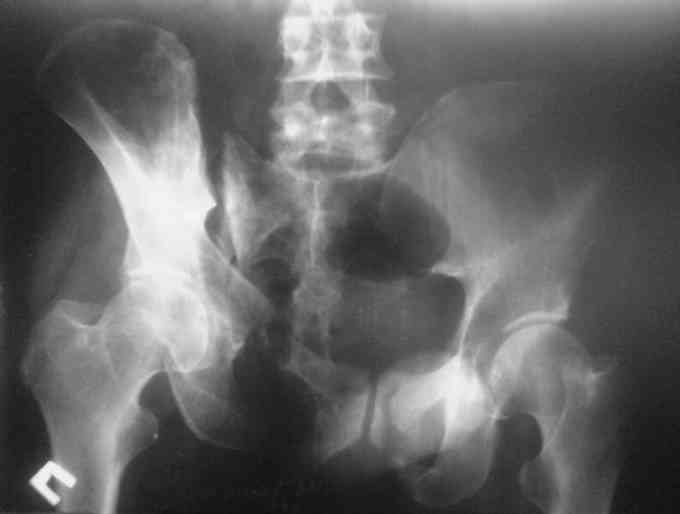

Здравствуйте, уважаемые коллеги. Ситуация такая. Мужчина 50 лет, невысокий, худой. Перелом костей таза пять месяцев назад. Пришел на костылях. В поисках адекватной помощи в краевых больницах был "переадресован" не ближе чем как в Курган и Москву. Денех естессно нет + семейные неурядицы в связи с приобретением статуса инвалида. Ехать, после хождений по мукам, теперь никуда не хочет. Готов на оперативное лечение в нашем отделении.Больной стабильный. Неврологического дефицита нет. Функции тазовых органов в норме.

Остается только вариант закрытого аппаратного лечения. В аттаче положение отломков на вытяжении в прямой (АР) проекции. Для сравнения снимок до и во время вытяжения.

Первоочередно для тазовых операций важно обследование, снимки таза в инлет, оутлет и прямая

На сравнительном снимке правый полутаз опустился

недостаточно, можно добавить вес и сделать все стандартные снимки.